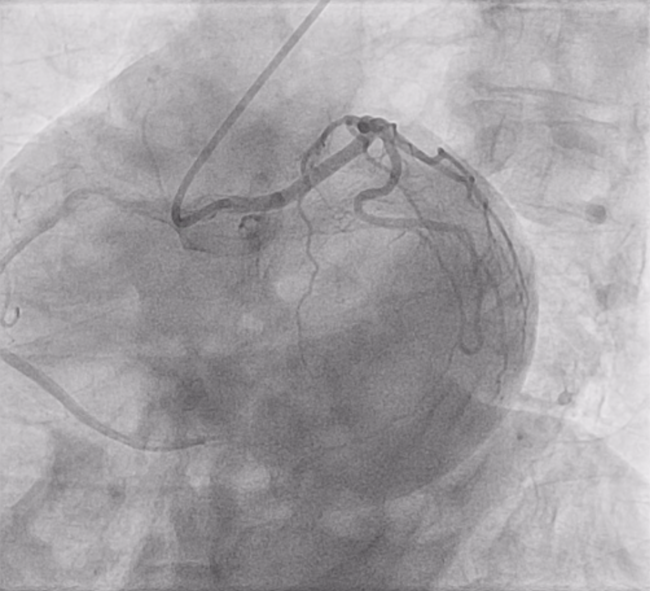

Here, we share a coronary angiography demonstrating anomalous left main (LM) coronary artery originating from the right coronary sinus in a 79-year-old male with no previous cardiac disease history (see below, Videos 1-5).

A 6 French AL1 guide catheter was used to engage the anomalous LM coronary artery originating from the right coronary cusp in this case.

Anomalous LM originating from the right sinus of Valsalva is a rare coronary anomaly. Anomalous LM is generally best engaged with an Amplatz Right (AR), short Amplatz Left (AL) such as an AL0.75 or AL1, or with a multipurpose catheter with clockwise maneuvering. Further evaluation of an anomalous LM to accurately delineate the course is generally recommended with a computed tomography or magnetic resonance imaging scan.